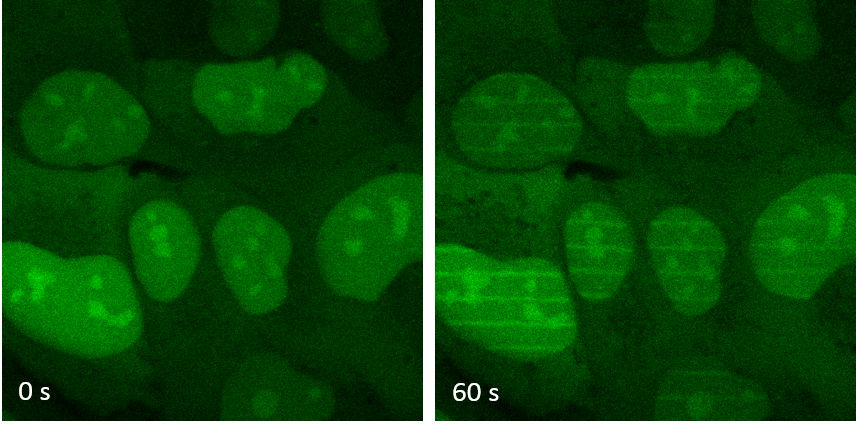

Figure 2: Cells containing the XLF protein marked in green (left) are irradiated by laser to create DNA breaks along thin lines. The proteins are recruited in one minute on the parallel lines drawn by the laser (right). © PCalsou / JBCharbonnier